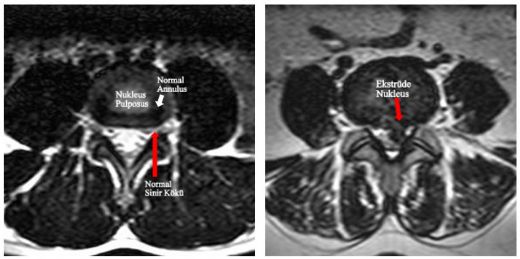

Bel Fıtığı Yırtılmasının Tanısı Bel fıtığı yırtılması tanısı, genellikle fiziksel muayene ve görüntüleme yöntemleri ile konur. Doktor, hastanın belirtilerini değerlendirir ve aşağıdaki testleri isteyebilir: